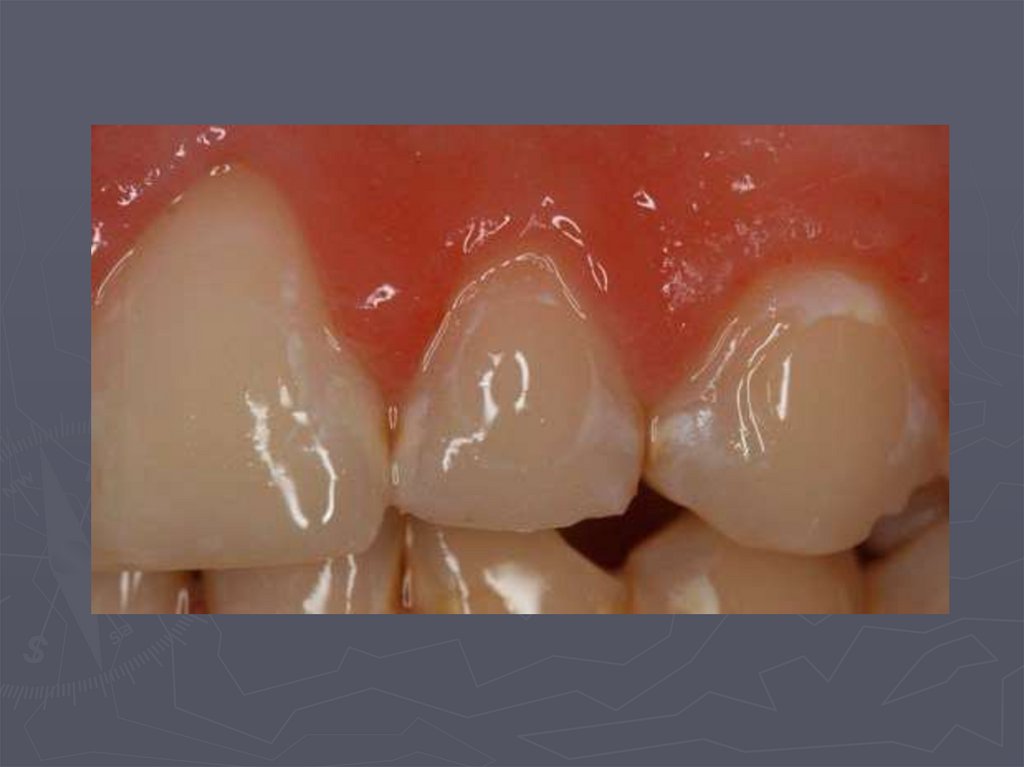

Циркулярный кариес

8. Циркулярный кариес

► нередко кариес начинается в пришеечной области;

► процесс распространяется вокруг всей коронки;

► формируется циркулярный кариес.